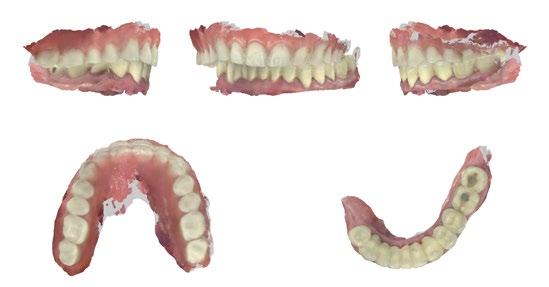

Empezaremos por un protocolo de fotografía intraoral que nos permita ver la situación inicial del paciente y que a su vez nos sirva de prueba legal ante cualquier tipo de reclamación. (Figuras 1 a 3)

Por otro lado, es imprescindible y fundamental realizar un CBCT de la arcada a tratar para poder visualizar los tejidos duros y hacer una primera valoración del lecho implantario y de la patología existente. (Figura 4)

Otra prueba imprescindible hoy en día para nosotros es la realización de un escaneado intraoral que nos aporte la información de los tejidos superficiales y fusionado con el CBCT nos permita valorar los tejidos blandos del paciente. (Figura 5)